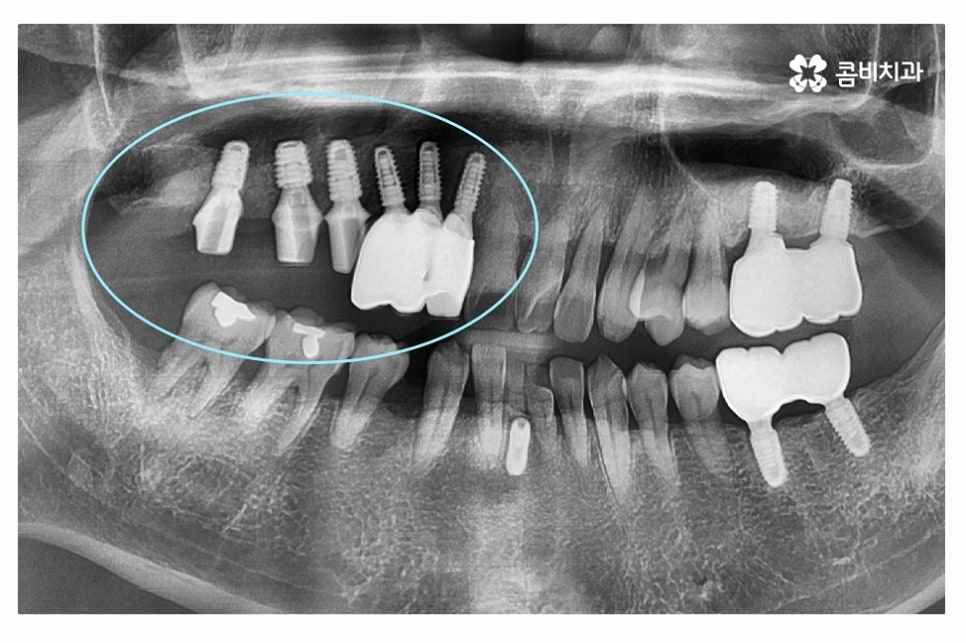

위 이미지처럼 인공치근이 잇몸뼈와 단단하게

골 유착 과정을 거치면 자연치아와 거의 비슷한 수준의 저작력을 회복할 수 있어요.

수술이 잘 된 경우 환자분의 치아의 모양에 맞게 어버트먼트를 제작하기 위하여

위 사진처럼 코핑이라는 것을 연결하고 임상을 뜨는 과정을 거친다고 볼 수 있어요